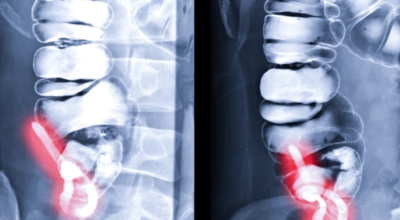

맹장은 소장의 말단부에서 대장으로 행하는 부위에 위치합니다. 주머니처럼 생겼고 소장에서 소화된 음식물이 이곳으로 넘어옵니다. 한편 충수는 10cm 정도 길이로 사람과 고등 영장류에게만 있고 이 충수의 입구가 막히거나 내용물을 맹장으로 보내지 못한다면 염증이 발생하는 것으로 보입니다. 이런 경우 대부분 수술적 절제가 필요한 급성 복통을 일으킵니다.

맹장염은 모든 연령대에서 일어날 수 있지만 2세 미만의 어린이에게는 발병률이 드물면서 10세에서 30세 사이의 연령대에 영향을 미칠 가능성이 가장 높다고 하는데요 이러한 맹장염에 걸리게 되는 주 까닭으로는 맹장 내부가 점액, 대변 및 기생충과 같이 팽창을 유발하는 성분으로 가득 차 있을 때 발생합니다. 맹장염은 맹장이 막힐 때, 대변등의 노폐물, 불순물이나 암에 의하여 생기게 될 수 있답니다. 맹장은 인체의 침투하는 바이러스 감염에 반응해서 부풀어 오를 수 있으므로 각종 세균으로 인한 감염으로 인하여 막힐 수도 있어요

맹장염의 통증은 90%이상이 오른쪽 아랫배 부위에서 일어나며 처음에는 배꼽주변에서부터 통증을 느끼기 시작하다가 아랫배쪽으로 옮겨가기 시작합니다. 맹장염은 일반 복통과는 다르게 오른쪽 아래 부위에서 다리나 배쪽으로 점점 고통의 범위가 확장한다는 성격이 있다고 하며 하나의 포인트로는 맹장염은 기침이나 재채기가 나오기도하며 차에서 멀미를 할때의 묘한 불쾌감도 느껴지기도 해요

충수돌기가 위치하는 오른쪽 아랫배에 통증이 발생하는 증상이 일반적이예요. 아랫배에 통증이 느껴지는 부위를 누르면 통증이 더 극심해 지는데요. 매우 드물게 충수가 왼쪽에 있는 사람도 있다고 하죠.